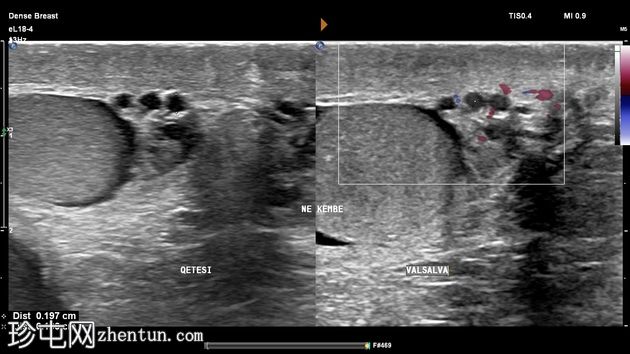

仰卧位静息状态和站立进行Valsalva动作时,蔓状静脉丛直径均保持在1.9毫米以内,因此排除精索静脉曲张。